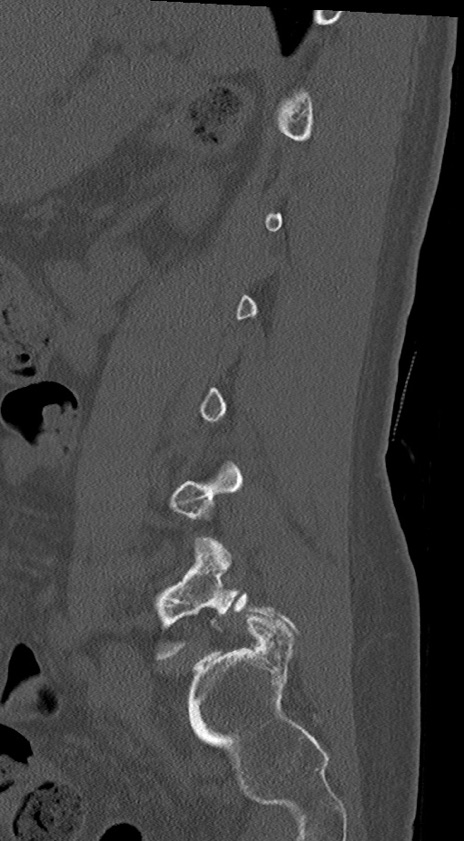

腰椎CT

冠状断像